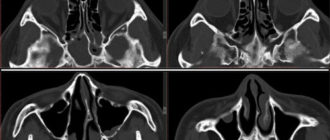

Сфеноидит — что это такое, симптомы и лечение у взрослых, хронический сфеноэтмоидит, признаки, темпорально-сфеноидальная